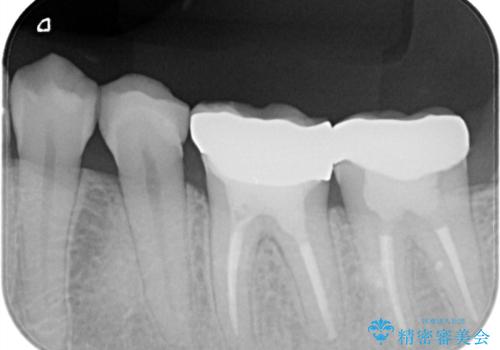

- 金属冠を白くしたいことを主訴に来院されました。

オールセラミッククラウン(st)にて修復しております。

根管治療も合わせて行なっているため、期間がかかっております。